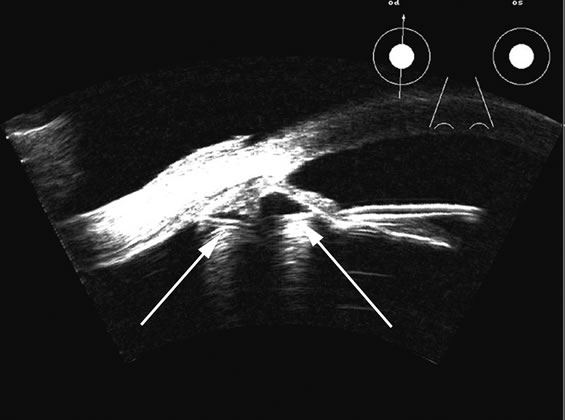

Hypotony is easily diagnosed by direct measurement of intraocular pressure, but the underlying cause is difficult to evaluate.11 High-frequency ultrasound scans can easily reveal separation of the ciliary body and the sclera. This allows different forms of hypotony to be determined—for example: tractional with membrane attached; primary as idiopathic, often inflammatory or hemorrhagic; and dehiscence secondary to iridodialysis or scleral perforation (Fig. 6). |